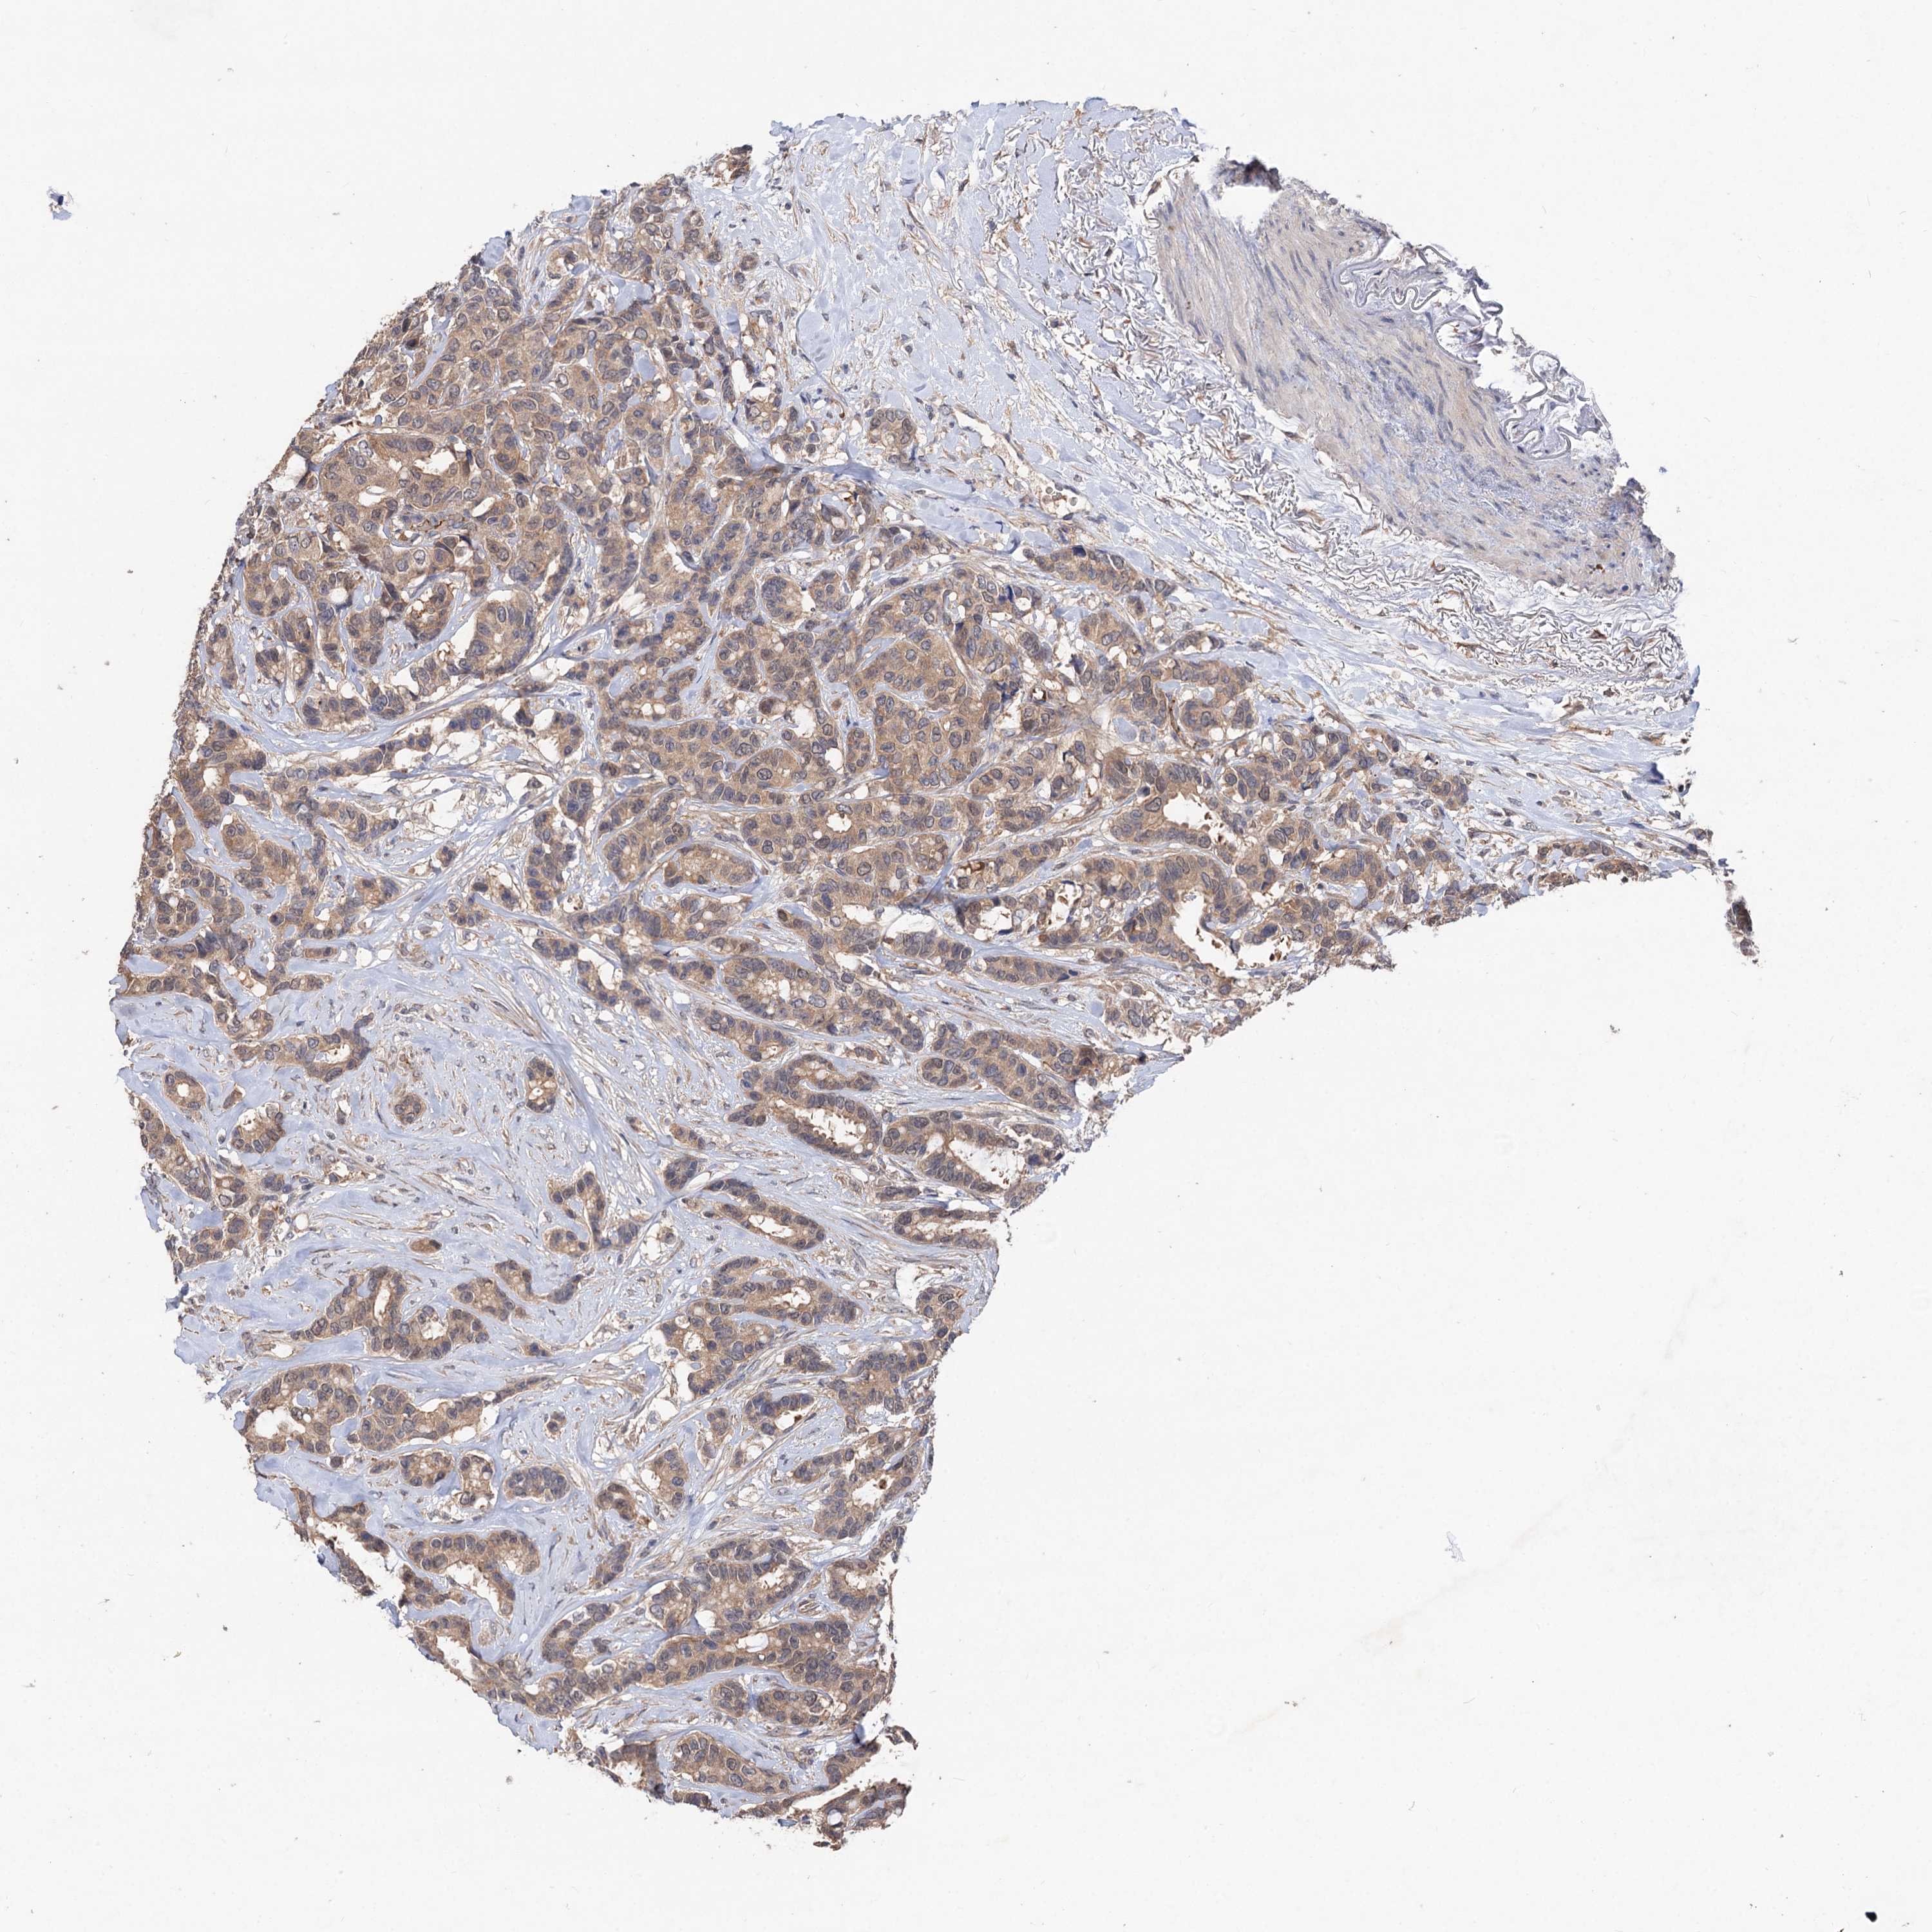

CANCER BREAST CANCER Show tissue menu

BRCA TCGA BRCA VALIDATION PROTEIN EXPRESSION